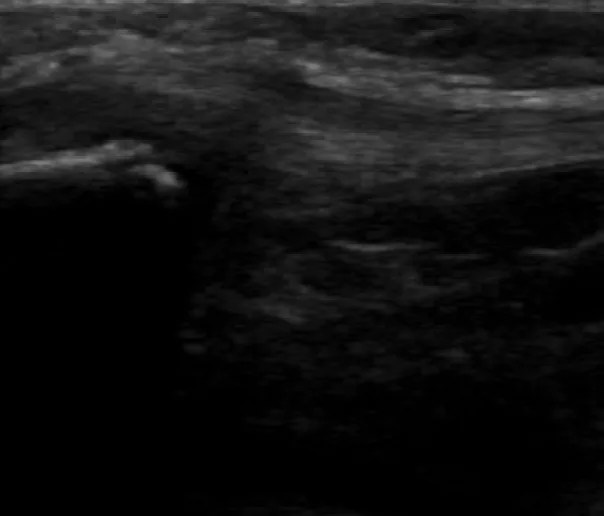

腫れはそこまで出ていなかったので、骨折か捻挫の判断をするためにエコー検査を行いました。

エコー検査では、右腓骨遠位端部に裂離骨折像が確認できたため、ギプス処置を施しました。ギプス固定でも、固定中に超音波骨折治療器(LIPUS)を行うために有窓ギプスにしました。LIPUSは週4〜5回照射(20分)行うことによって骨癒合期間が40%短縮されると報告されています。